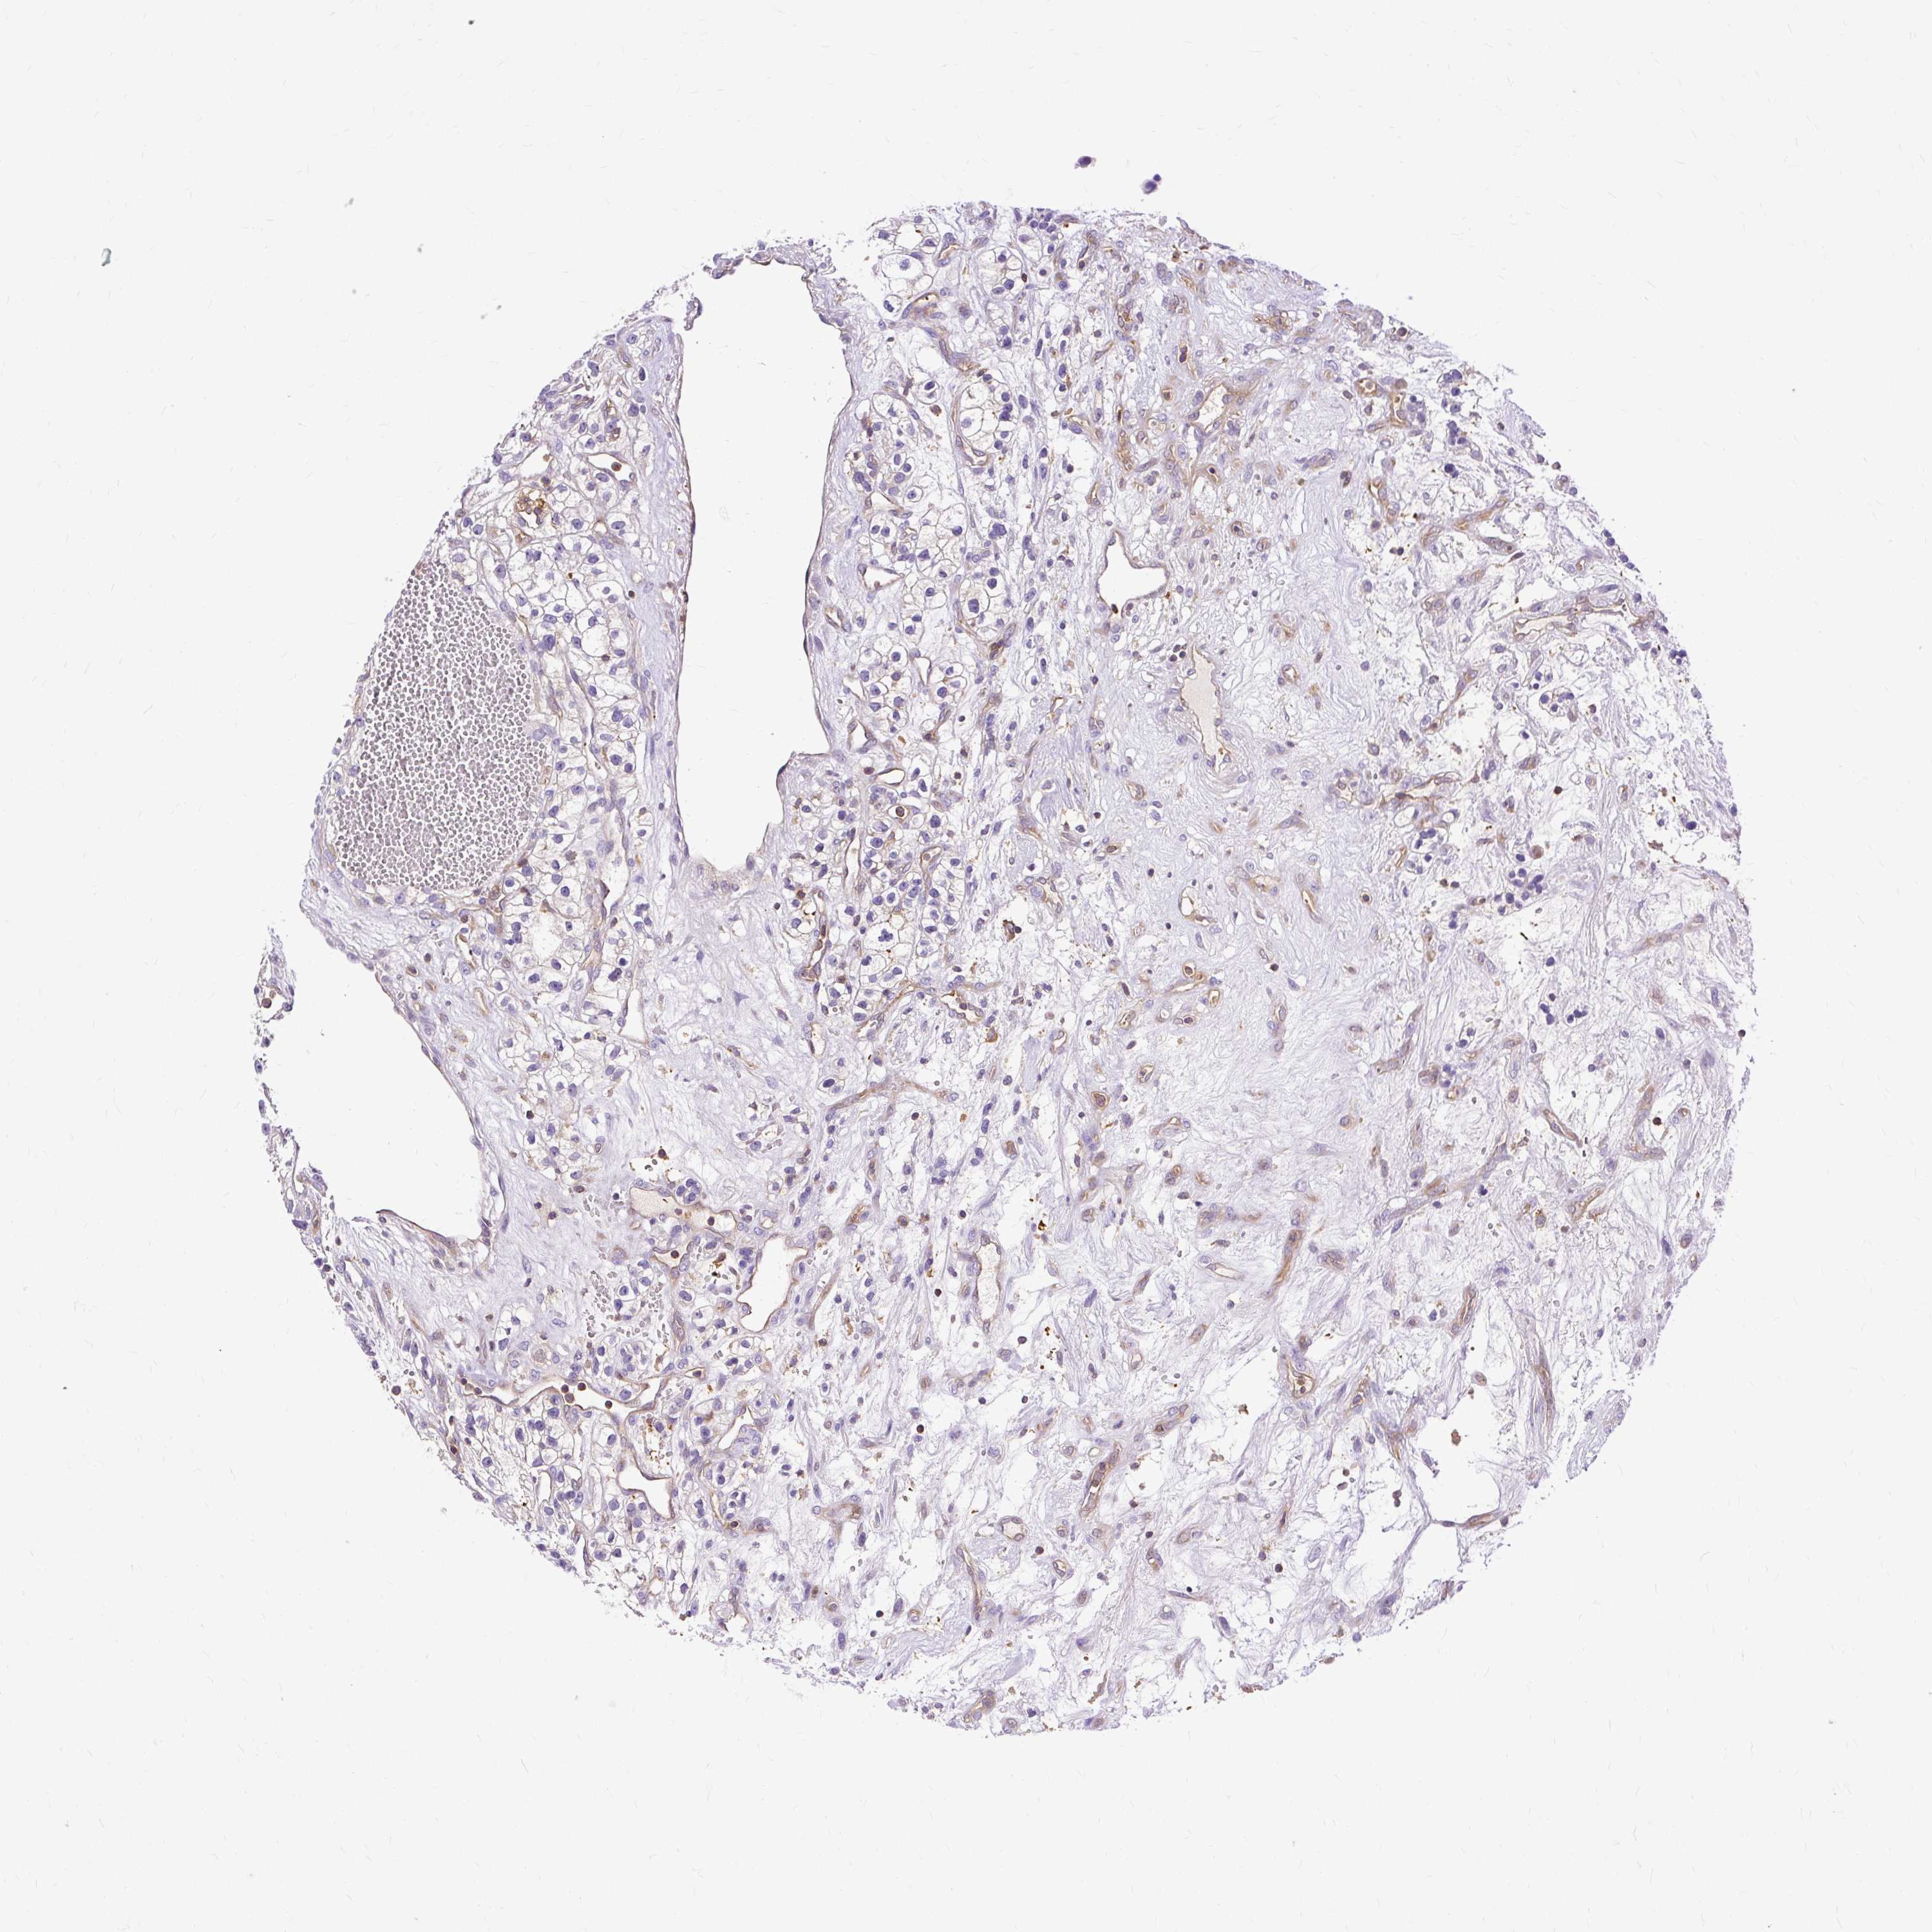

KIDNEY RENAL CLEAR CELL CARCINOMA (VALIDATION) - Interactive survival scatter ploti

The Survival Scatter plot shows the clinical status (i.e. dead or alive) for all individuals in the patient cohort, based on the same data that underlies the corresponding Kaplan-Meier plots. Patients that are alive at last time for follow-up are shown in blue and patients who have died during the study are shown in red.

The x-axis shows the expression levels (FPKM) of the investigated gene in the tumor tissue at the time of diagnosis. The y-axis shows the follow-up time after diagnosis (years). Both axes are complimented with kernel density curves demonstrating the data density over the axes. The top density plot shows the expression levels (FPKM) distribution among dead (red) and alive patients (blue). The right density plot shows the data density of the survived years of dead patients with high and low expression levels respectively, stratified using the cutoff indicated by the vertical dashed line through the Survival Scatter plot. This cutoff is automatically defined based on the FPKM cutoff that minimizes the p-score. The cutoff can be changed by dragging the vertical line or by entering a cutoff value in the square labeled "Current cut-off".

Under the Survival Scatter plot the p-score landscape (black curve; left axis) is shown together with dead median separation (red curve; right axis). Dead median separation is the difference in median mRNA expression between patients who have died with high and low expression, respectively. It is calculated as follows: median FPKM expression of dead patients with high expression - median FPKM expression of dead patients with low expression. This is intended to aid the user in visually exploring custom cutoffs and the associated p-scores and dead median separation.

Individual patient data is displayed and can be filtered by clicking on one or more of the category buttons on the top of the page. Categories describing expression level and patient information include: high, low, alive, dead, female, male and tumor stages. The scale of the x-axis can be toggled between linear and log-scale by clicking on the "x log" button. Mouse-over function shows TCGA ID, patient information and mRNA expression (FPKM) for each patient.

& Survival analysisi

Kaplan-Meier plots summarize results from analysis of correlation between mRNA expression level and patient survival. Patients were divided based on level of expression into one of the two groups "low" (under cut off) or "high" (over cut off). X-axis shows time for survival (years) and y-axis shows the probability of survival, where 1.0 corresponds to 100 percent.

TWF2 is not prognostic in Kidney Renal Clear Cell Carcinoma (validation)

Best expression cut offi

: 33.69

P scorei

N/A

Average pTPM 41.0

Number of samples 100